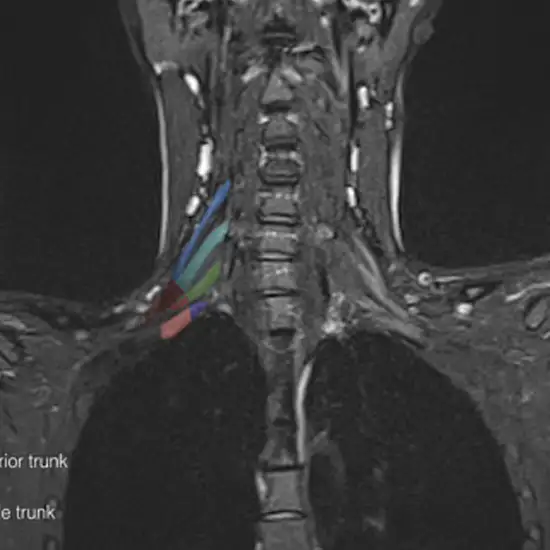

MRI of the right brachial plexus shows the nerve junction network (which connects to the knee, thigh, belly, calves, back, and groin) and surrounding soft tissues.

MRI (Magnetic Resonance Imaging) spine is a non-invasive medical diagnostic tool used to obtain detailed images of the brachial plexus and surrounding tissue. MRI of the Brachia Plexus is used to show abnormalities in the nerve junction network (which connects to the knee, thigh, belly, calves, back, and groin) and surrounding soft tissues.